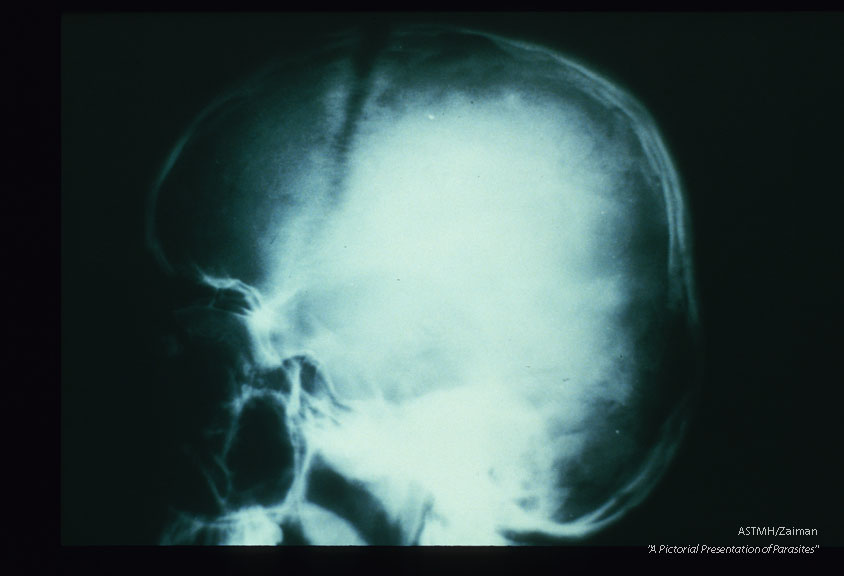

Frontal and lateral views of the skull of a young teenage boy show separation of bones of the skull with widening of the sutures. The widened sutures appear as irregular wavy black lines. Separation of the skull plates was due to increased intra-cranial pressure caused by a growing Echinococcus cyst. This boy also had a liver cyst. Both cysts were successfully removed surgically.

Echinococcus granulosus